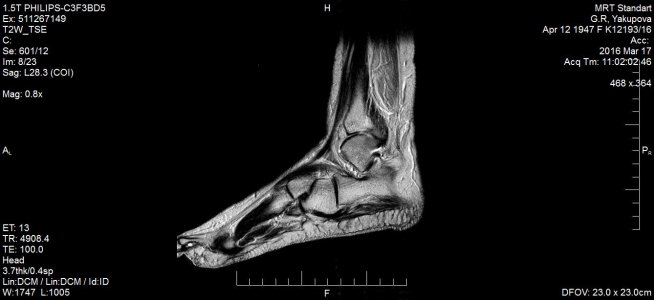

16 марта МРТ заключение: МР- картина консолидирующегося краевого косого перелома дорзальных отделов медиальной лодыжки /без смещения - перелом пилона тип В1 по АО/; остеоартроза голеностопного сустава и стопы: минимального синовита голеностопного сустава. Признаки отека мягких тканей области голеностопного сустава. (фото № 2)